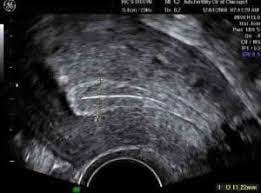

Detect the fetal heartbeat at 6 weeks

The NHS will invite you for your first scan at around 10-14 weeks. However, if you’ve had trouble conceiving in the past and would like the peace of mind that things are progressing well, it is possible to have this at six weeks at a private clinic.

A 6-week ultrasound scan is also instrumental for detecting ectopic pregnancy, which poses a particular risk to women opting for assisted reproduction.

Even if you have conceived naturally, 6 weeks scans are highly recommended as they can detect a blighted ovum, which is the cause of 50% of miscarriages.